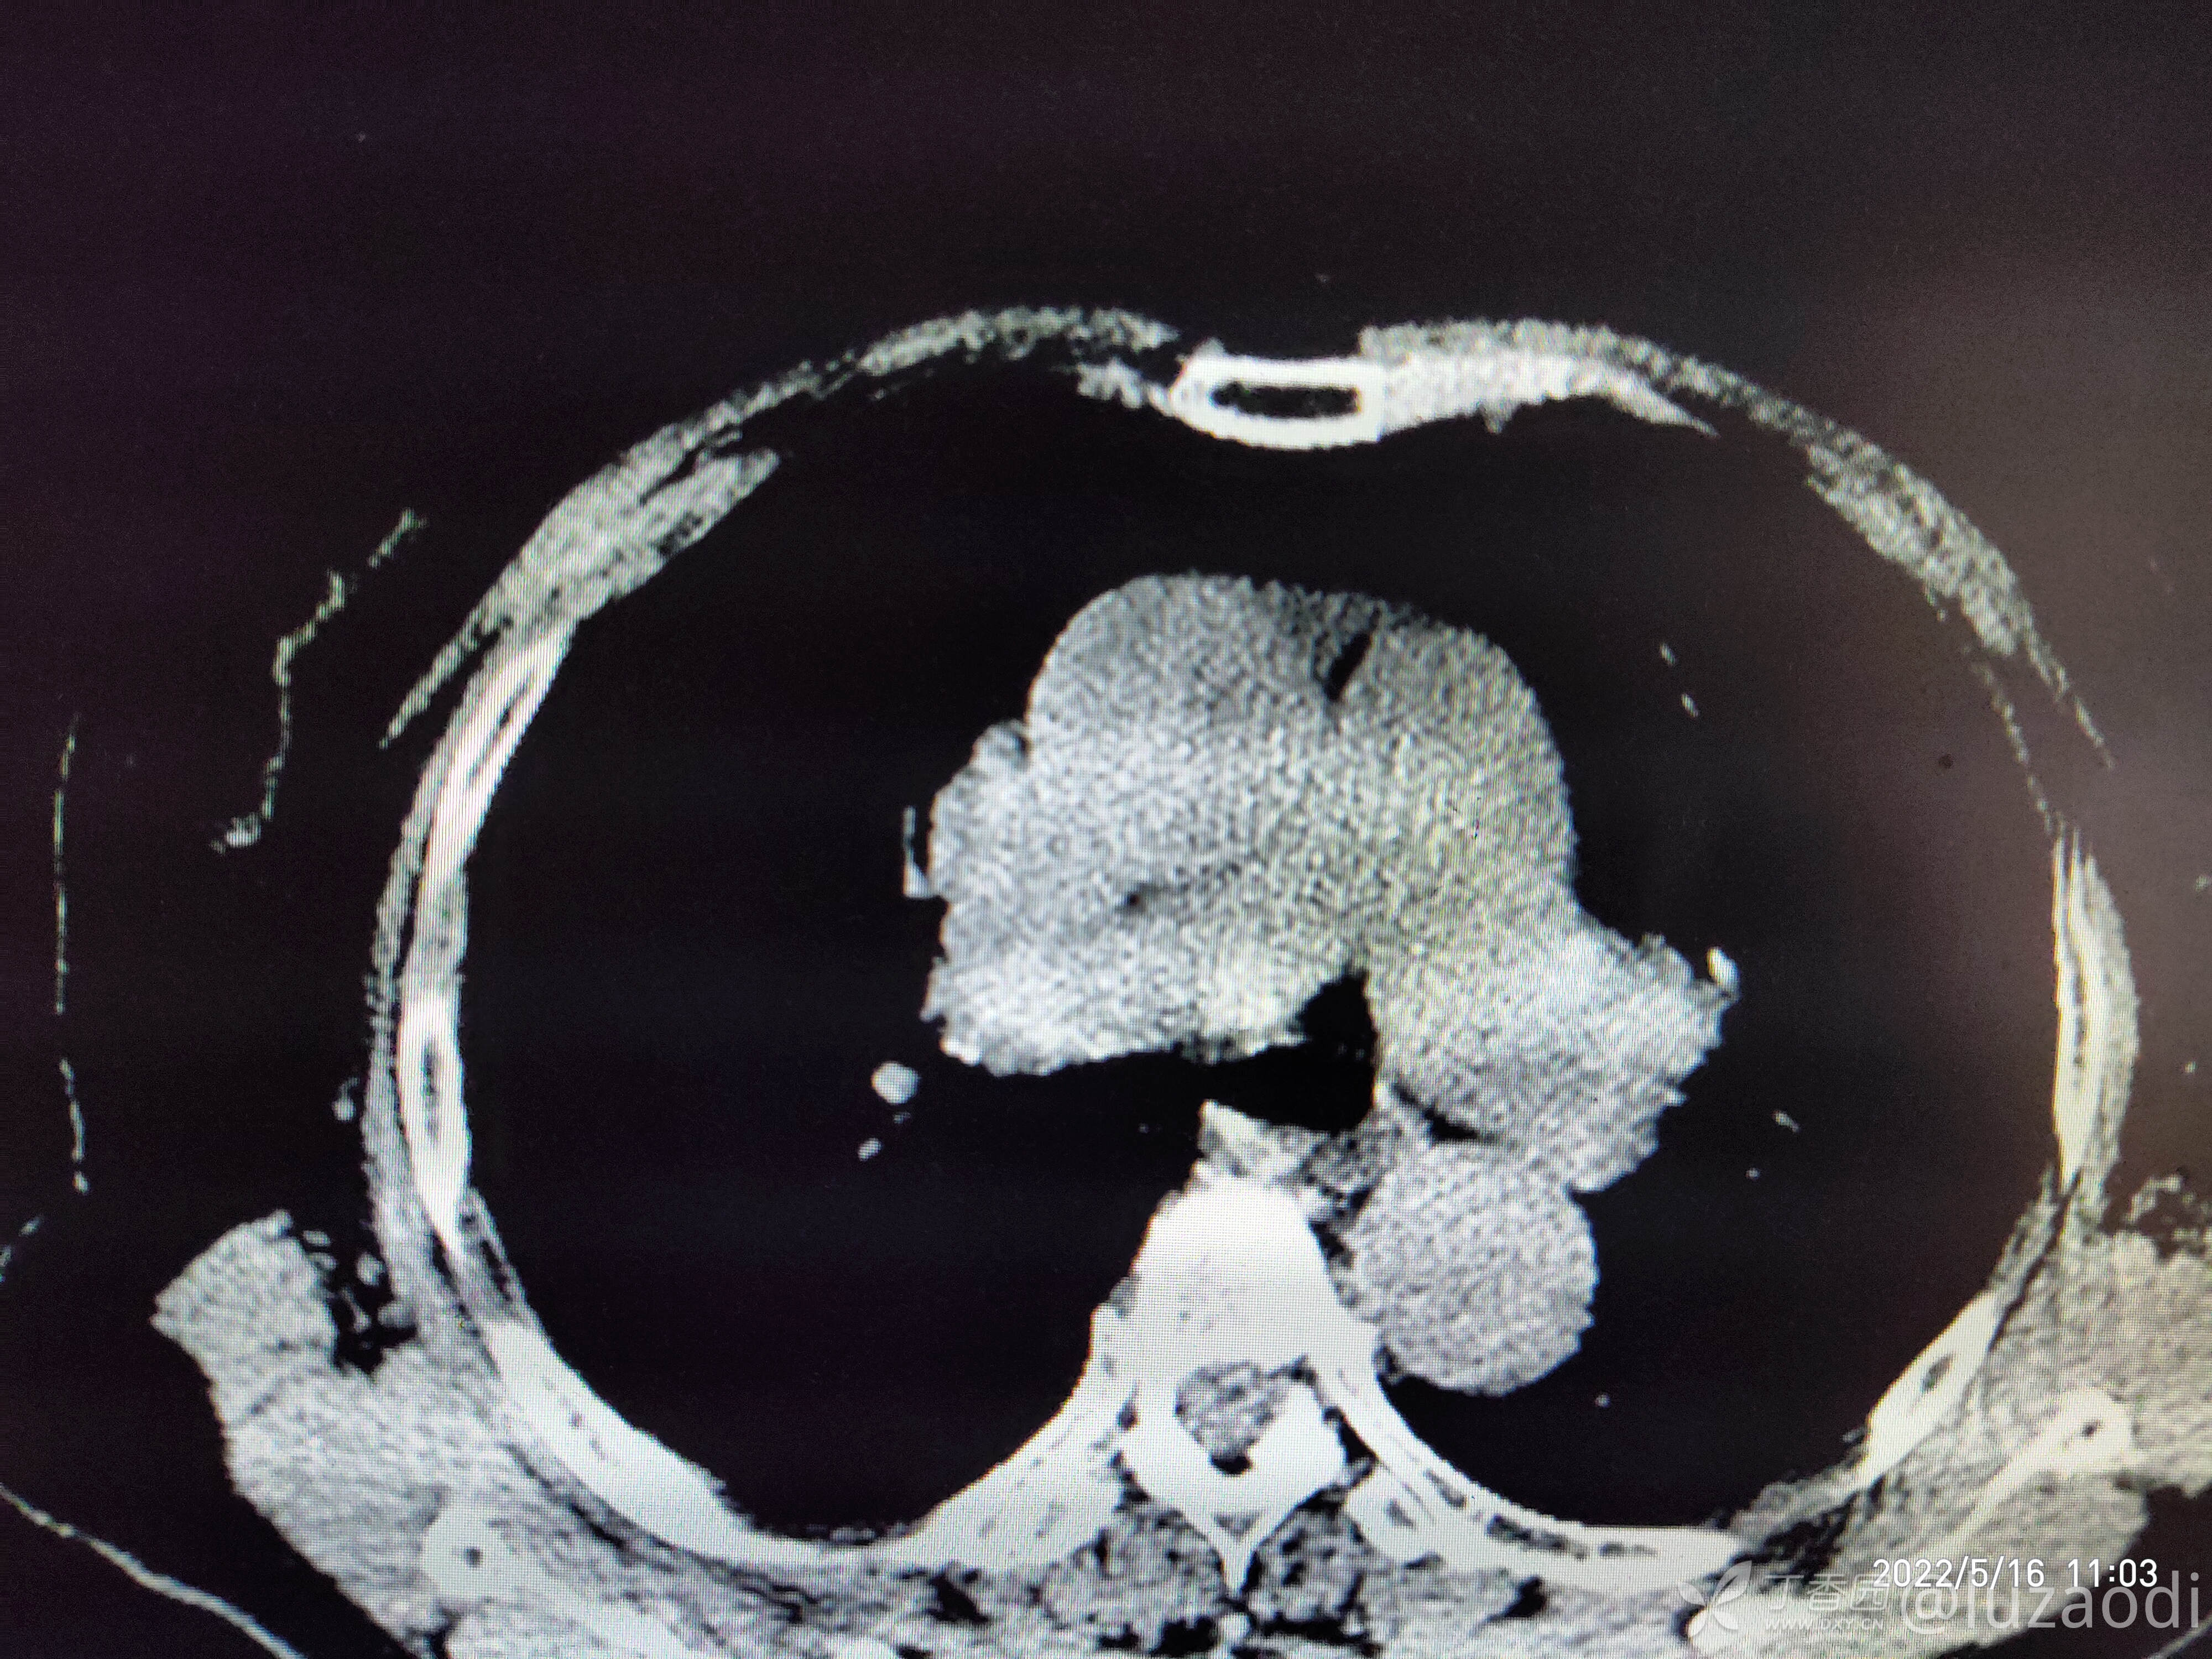

治疗经过:入院后患者仅有乏力,未见明显神经定位征。近期无发热、咳嗽、腹泻症状。遂予血糖、心电图、生化检查及影像检查,结果如下:

我去。。。。。视频只能上传一个,头颅CT上传不了,我直接说报告吧。头颅CT报腔隙性脑梗。

到目前为止,所有的资料如上面所描述。那么请大家讨论一下这个病人可能是何种疾病,下一步应该怎么做?如何告知患者病情以及可能的风险?欢迎各位新手和老鸟留言讨论,看看大家的思维及诊疗,或者是指出到目前为止还有什么需要做的诊疗措施?错也不要紧,没有错哪有对?在我这错好过在病人身上错。要学技术就不能要脸,各位